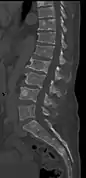

Medical imaging

The diagnostic examination of a person with suspected multiple myeloma typically includes a skeletal survey. This is a series of X-rays of the skull, axial skeleton, and proximal long bones. Myeloma activity sometimes appears as "lytic lesions" (with local disappearance of normal bone due to resorption) or as "punched-out lesions" on the skull X-ray ("raindrop skull"). Lesions may also be sclerotic, which is seen as radiodense.[70] Overall, the radiodensity of myeloma is between −30 and 120 Hounsfield units (HU).[71] Magnetic resonance imaging is more sensitive than simple X-rays in the detection of lytic lesions, and may supersede a skeletal survey, especially when vertebral disease is suspected. Occasionally, a CT scan is performed to measure the size of soft-tissue plasmacytomas. Nuclear Medicine Bone scans are typically not of any additional value in the workup of people with myeloma (no new bone formation; lytic lesions not well visualized on nuclear bone scan).